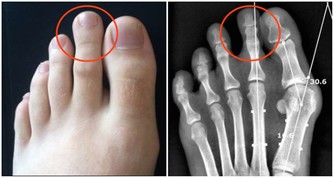

另外,包皮過長、包莖、陰莖炎症以及泌尿系感染、尿道結石也可能出現小便分叉,後者常伴有尿急尿痛等其他不適。